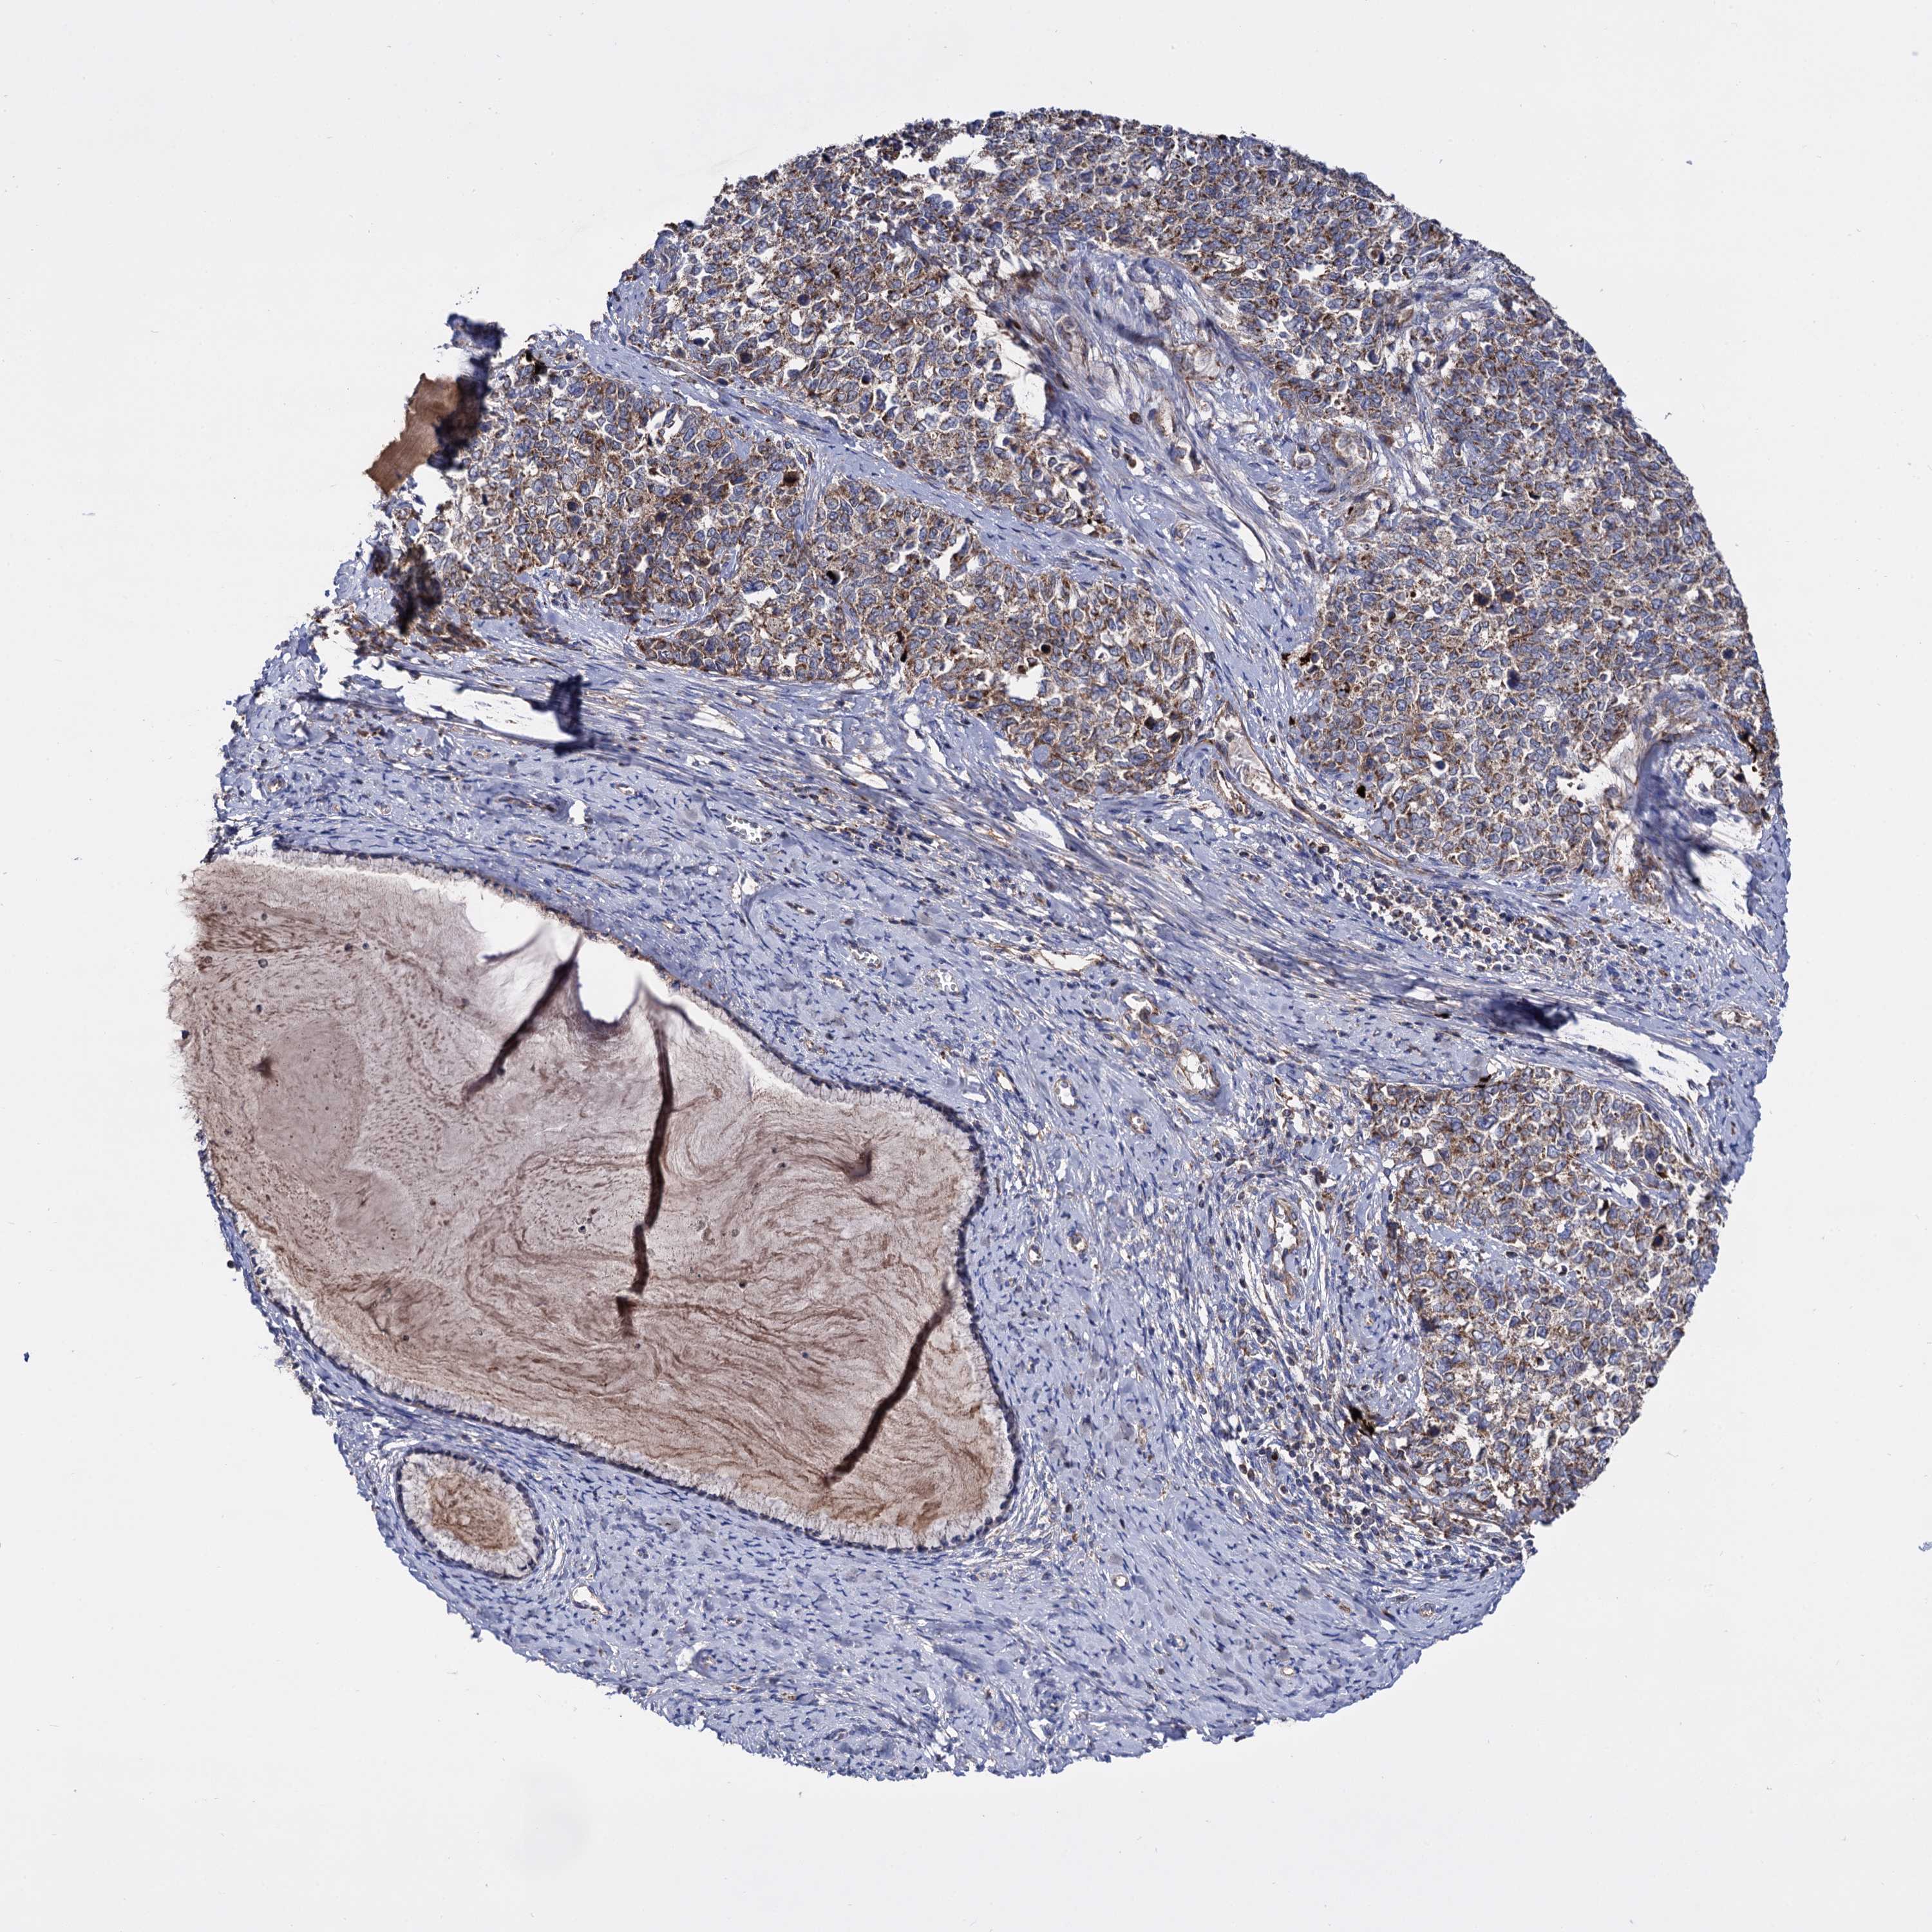

CERVICAL CANCER - Protein expressioni

A mouse-over function shows sample information and annotation data. Click on an image to view it in a full screen mode. Samples can be filtered based on level of antibody staining by selecting one or several of the following categories: high, medium, low and not detected. The assay and annotation is described here.

Note that samples used for immunohistochemistry by the Human Protein Atlas do not correspond to samples in the TCGA dataset.

Antibody stainingi

Antibody staining in the annotated cell types in the current human tissue is reported as not detected, low, medium, or high, based on conventional immunohistochemistry profiling in selected tissues. This score is based on the combination of the staining intensity and fraction of stained cells.

Each image is clickable and will lead to virtual microscopy that enables deeper exploration of all samples and also displays staining intensity scores, fraction scores and subcellular localization as well as patient and tissue information for each sample.

Antibody HPA040845

Staining

High

Medium

Low

Not detected

Intensity

Strong

Moderate

Weak

Negative

Quantity

>75%

75%-25%

<25%

None

Location

Nuclear

Cytoplasmic/membranous

Cytoplasmic/membranous,nuclear

Squamous cell carcinoma, NOS

Adenocarcinoma, NOS